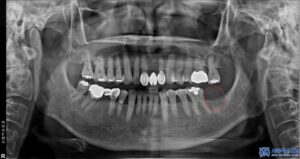

환자분은 좌측 아래쪽 어금니가 없는 상태였고,

오랫동안 방치되어 치조골(잇몸뼈)의

변화가 일부 있었습니다.

하지만 다행히도 임플란트를 식립하기에

충분한 골량이 유지되고 있었고,

무절개 방식으로 빠르게

임플란트를 진행할 수 있었습니다.

임플란트 치료 외에도, 환자분의 남아있는

치아들 중 심한 충치가 있는 어금니

(오른쪽 위 큰 어금니, 왼쪽 위 작은 어금니,

왼쪽 위 큰 어금니, 왼쪽 아래 큰 어금니)는

신경치료를 진행하였습니다.